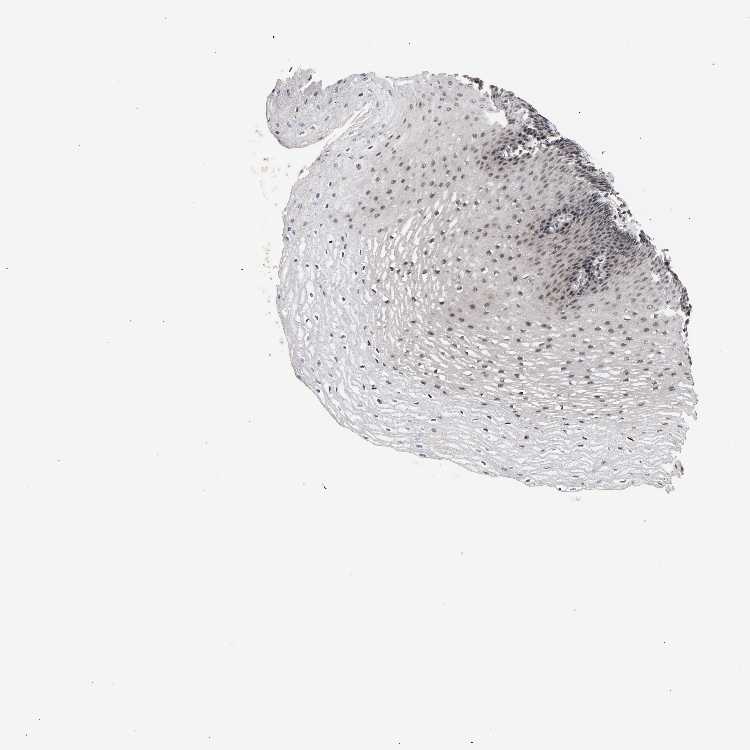

ESOPHAGUS - Antibody stainingi

Antibody staining in the annotated cell types in the current human tissue is reported as not detected, low, medium, or high, based on conventional immunohistochemistry profiling in selected tissues. This score is based on the combination of the staining intensity and fraction of stained cells.

Each image is clickable and will lead to virtual microscopy that enables deeper exploration of all samples and also displays staining intensity scores, fraction scores and subcellular localization as well as patient and tissue information for each sample.

Antibody CAB019271

Squamous epithelial cells Medium